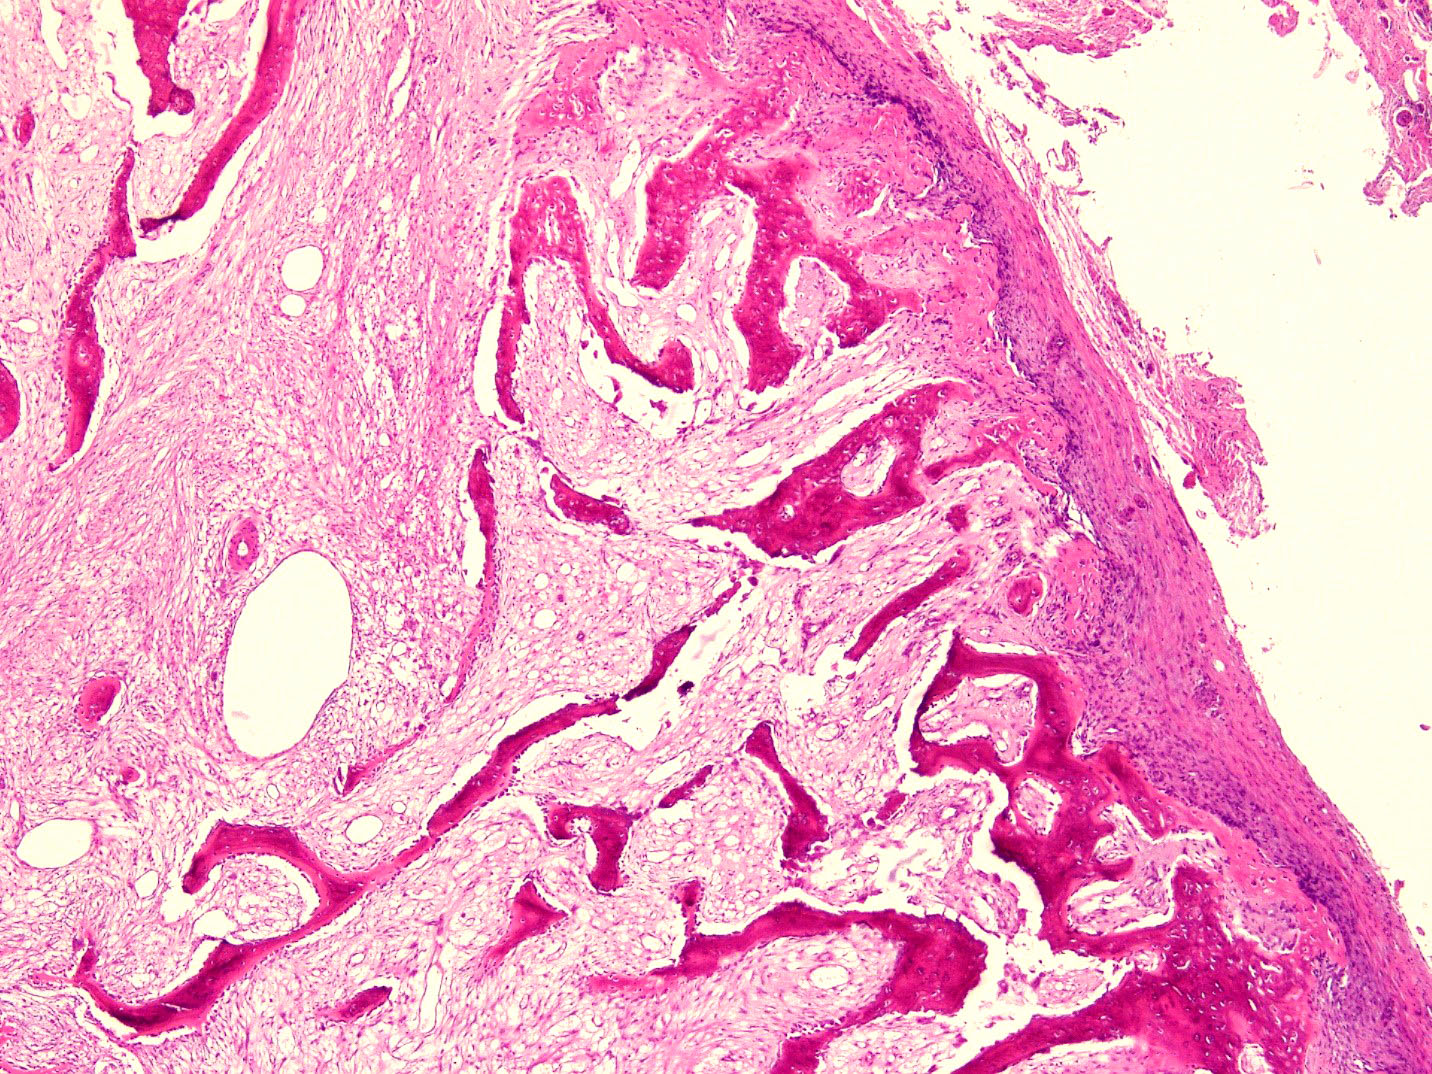

- Histologically, zonal pattern is characteristic with different degrees of cellular differentiation (inner zone, intermediate zone and peripheral zone)

- Inner central zone:

- Composed of fibroblastic / myofibroblastic proliferation, which is richly vascular, rich in inflammatory cells and resembles nodular fasciitis; some multinucleated giant cells may also be seen

- Cells show mild degree of pleomorphism and brisk mitosis

- Areas of hemorrhage, fibrin, endothelial proliferation and entrapped atrophic muscle fibers are noted

- Intermediate zone:

- There is a mixture of fibroblasts and osteoblasts along with erratic osteoid separated by small sized vessels

- Scattered chondrocytes may be appreciated

- Peripheral zone:

- Osteoid undergoes calcification and leads to lamellar bone formation

- Islands of mature or immature cartilage may be present

- Extreme periphery / margin shows mature bone with osteoblastic rimming and little to no pleomorphism

- Lesion is separated from the normal tissue (muscle) by a zone of loose, myxoid fibrous tissue

Microscopic (histologic) images

A 36 year old boxer presented with a painful mass in the right arm for the last 1.5 months. On radiology, an intramuscular mass was seen with peripheral mineralization and central latency. It was biopsied, which showed the morphology in the image above. What is the most likely diagnosis?

B. Myositis ossificans. The given history in this case shows that the patient is physically active and provides short duration history of the lesion. The radiological findings suggest a lesion with maturation at periphery. The microscopic image shows characteristic zonation. These are all features of myositis ossificans.